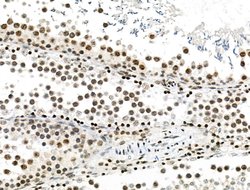

Invitrogen™ Phospho-PDX1 (Ser66) Polyclonal Antibody

Antibody detects endogenous levels of PDX1 only when phosphorylated at Ser66.

| Immunohistochemistry (Paraffin), Western Blot, Immunocytochemistry | |

| Human, Mouse, Rat | |